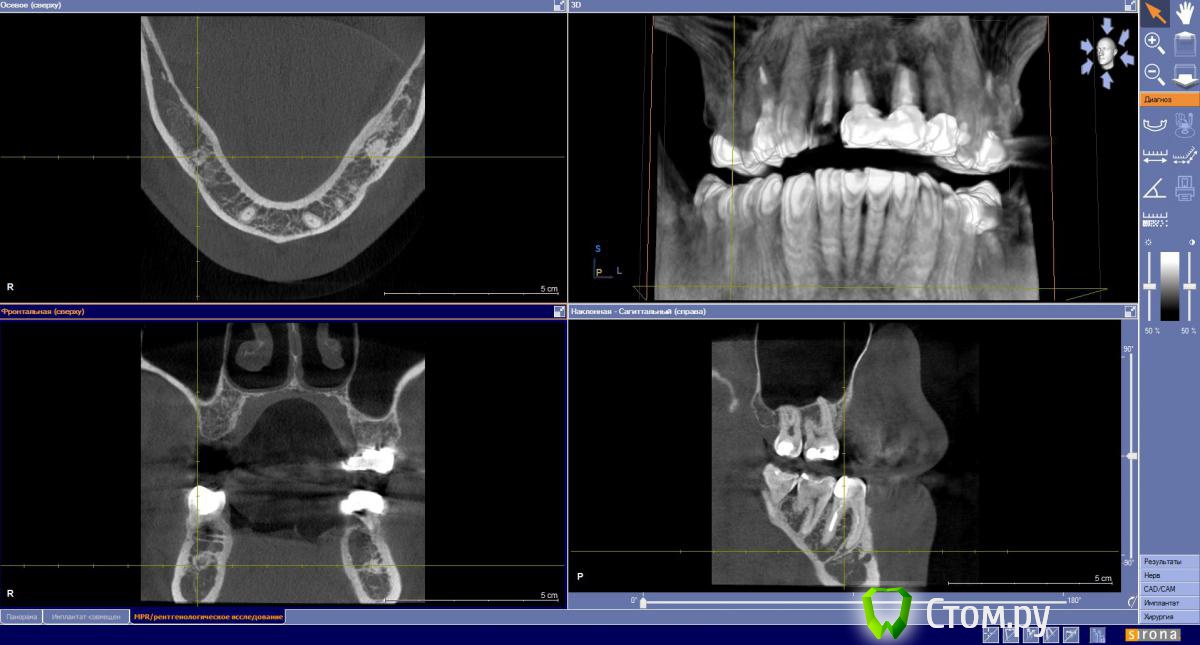

Sergei27 Опубликовано 31 августа, 2014 Поделиться Опубликовано 31 августа, 2014 В полости рта после жесткой пищи напротив зуба 4,6 возникаем мешочек 5мм. При надавливании лопается, ранка заживает, было уже 3 раза примерно 90, 60 и 25 дней назад. Что это, киста? Можно ли пере лечить канал или удалять зуб? Ссылка на комментарий

Sergei27 Опубликовано 19 сентября, 2014 Автор Поделиться Опубликовано 19 сентября, 2014 ПерелечиватьКанал до конца пройти не удается, склерозировал. Еще 5 мм. Наверное надо удалять Ссылка на комментарий